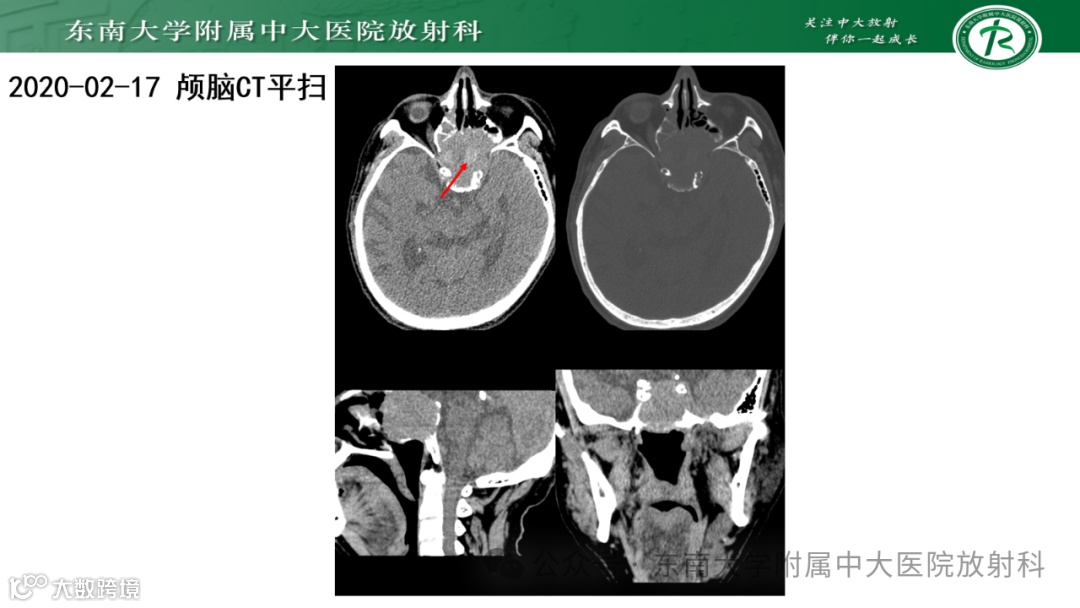

病例3——脊索瘤